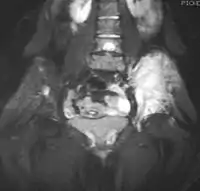

![]() Рентгенографічна картина ураження великогомілкової кістки саркомою Юїнга в дитини. Пухлина показана стрілкою Рентгенографічна картина ураження великогомілкової кістки саркомою Юїнга в дитини. Пухлина показана стрілкою | |

Для уточнення розмірів пухлини, а також для виявлення віддалених метастазів у діагностиці саркоми Юїнга застосовують комп'ютерну томографію органів грудної клітки, а також ділянок скелету та інших ділянок тіла, уражених пухлинним процесом або з імовірністю метастазування в цю ділянку. Також для діагностики віддалених метастазів пухлини застосовують магнітно-резонансну томографію.[11][7] Для уточнення діагнозу можуть застосовувати також позитронну емісійну томографію.[11][7]